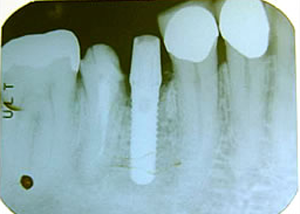

右下

第一第臼歯近心根破折

(大臼歯は歯根が二つに分かれている)

1.H18.4.12

抜歯後

(某歯科医院にて手前の歯根のみ抜歯)

2.インプラントする前

(抜歯後4ヶ月弱)

3.H18.8.22

抜いたところにインプラント埋入